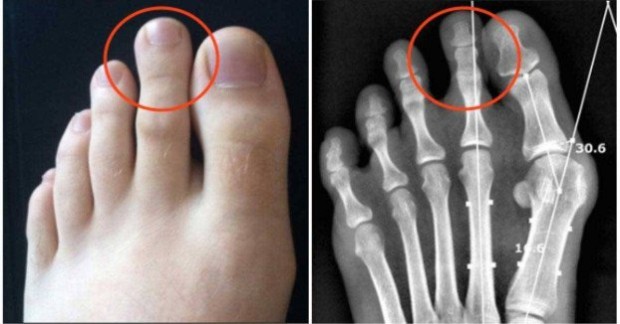

Grčko stopalo može donijeti probleme na nogu i uzrokovati bol, ukoliko se ne koristi adekvatna obuća.

Imajte na umu da, kada hodate ili trčite, vaše noge trpe većinu tjelesne težine, tako da je oblik stopala nešto što znatno utiče na cjelokupan osjećaj. Osobe sa grčkim stopalom češće trpe bolove u stopalima, a to je nešto što se ne smije ignorisati!

Ako imate grčko stopalo i patite od bolova, najbolja stvar za učiniti je posjetiti ljekara, kako bi se vaš slučaj dublje analizirao. Ne dozvolite da se stvar iskomplikuje!